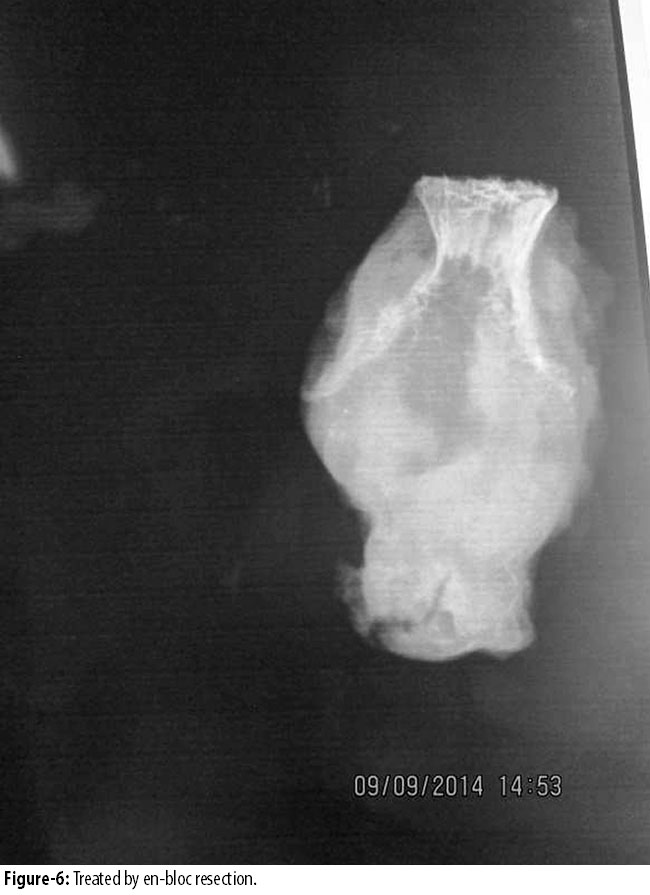

Duration of symptoms ranged from 4 to 12 months with a mean of 6.54 months (SD 4.08). All the tumours presented as expansile lesion, destroying cortex in 8(3.3%) cases. In all cases, lesion was more than half the diameter of the bone and thickness of sub-chondral bone in adjacent articular surface was less than 5mm to 0mm. All of them had extension into the soft tissue. Open biopsy was performed in 7(2.9%) cases. In 6(2.5%) cases, fine needle aspiration cytology (FNAC) was diagnostic, showing giant cell lesion. 1(0.4) calcaneal giant cell tumour was treated by extended curettage and filling the cavity with fibular head compact bone graft. Other 2(0.8%) cases of calcaneal giant cell tumour were treated by complete resection of calcaneus. 1(0.4%) case of talus GCT was treated by curettage and bone grafting. Out of 7(2.9%) cases of metatarsals, 4(1.6%) were in 1st metatarsals, 2(0.8%) in 2nd metatarsal and 1(0.4%) in 3rd metatarsal. 2(0.8%) GCTs in 1st metatarsal (Figure-3 and 4)

and 1(0.4%) in 2nd metatarsal were in stage3 (Figure 5 and 6),

and were treated by en-bloc resection and reconstruction with free fibular graft. Fibular graft was held with intramedullary K-wire. Rest of the tumours in all metatarsals were stage 2 and were treated by curettage and autologous cancellous bone grafting. In 2(0.8%) cases of phalanges, 1(0.4%) in proximal phalanx of big toe was treated by resection and fibular bone grafting and 1(0.4%) was treated by amputation of 3rd toe. There was 1(0.4%) recurrence in calcaneus and 1(0.4%) in 1st metatarsal, both of which were initially treated by curettage and bone grafting. Calcaneus recurrence was treated by below-knee amputation and 1st metatarsal recurrence by resection and iliac crest cortico cancellous bone graft.